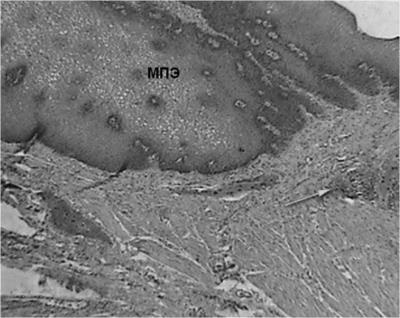

A szövettani vizsgálat a nyelőcső eltávolítása után végzett 3 esetben, a széleit a nyelőcső-mediasztinális sipoly után fibroezofagoskopii - 1 fő esetében. nyelőcső változások a stent minden esetben azonos, és képviseli a gyulladás különböző súlyosságú. A nyálkahártya talált szabálytalan hangsúlyos acanthosis, bazális réteg hiperaktivitás, dyskeratosis fejlesztésével a granulációs szövet a proximális és disztális végei a stent. A nyálkahártya alatti réteg feltárt infiltrációja limfociták, plazma sejtek és a makrofágok (ábra. 7).